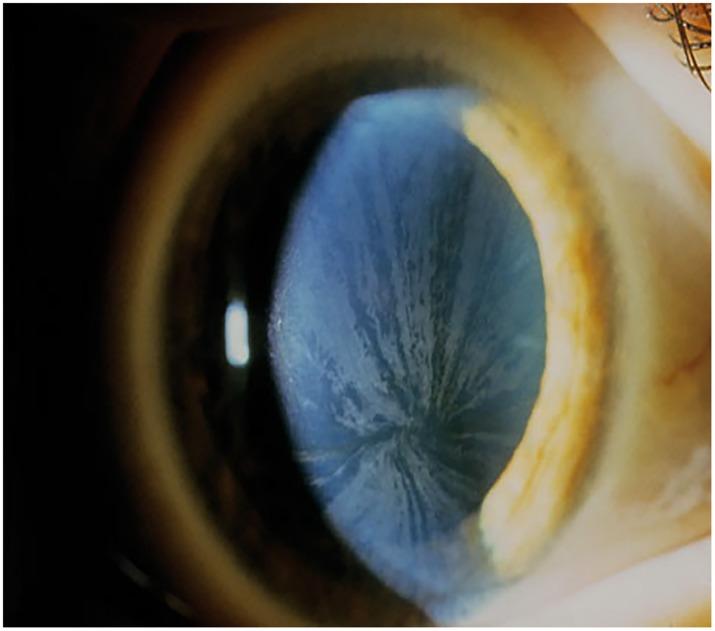

To investigate an influence of mucopolysaccharidosis (MPS)- and Morbus Fabry-associated corneal opacities on intraocular pressure (IOP) measurements and to evaluate the concordance of the different tonometry methods.

25 MPS patients with or without corneal clouding, 25 Fabry patients with cornea verticillata ≥ grade 2 and 25 healthy age matched controls were prospectively included into this study. Outcome measures: Goldmann applanation tonometry (GAT); palpatory assessment of IOP; Goldmann-correlated intraocular pressure (IOPg), corneal-compensated intraocular pressure (IOPcc), corneal resistance factor (CRF) and corneal hysteresis (CH) assessed by Ocular Response Analyzer (ORA); central corneal thickness (CCT) and density assessed with Pentacam. Statistical analysis was performed using linear mixed effect models and Spearman correlation coefficients. The concordance between tonometry methods was assessed using Bland-Altman analysis.

There was no relevant difference between study groups regarding median GAT, IOPg, IOPcc and CCT measurements. The limits of agreement between GAT and IOPcc/IOPg/palpatory IOP in MPS were: [-11.7 to 12.1mmHg], [-8.6 to 15.5 mmHg] and [- 5.4 to 10.1 mmHg] respectively. Limits of agreement were less wide in healthy subjects and Fabry patients. Palpatory IOP was higher in MPS than in healthy controls and Fabry patients. Corneal opacity correlated more strongly with GAT, IOPg, CH, CRF, CCT and corneal density in MPS (r = 0.4, 0.5, 0.5, 0.7, 0.6, 0.6 respectively) than in Fabry patients (r = 0.3, 0.2, -0.03, 0.1, 0.3, -0.2 respectively). In contrast, IOPcc revealed less correlation with corneal opacity than GAT in MPS (r = 0.2 vs. 0.4).

ORA and GAT render less comparable IOP-values in patients suffering from MPS-associated corneal opacity in comparison to Fabry and healthy controls. The IOP seems to be overestimated in opaque MPS-affected corneas. GAT, IOPg and biomechanical parameters of the cornea correlate more strongly with the corneal clouding than IOPcc in MPS patients.